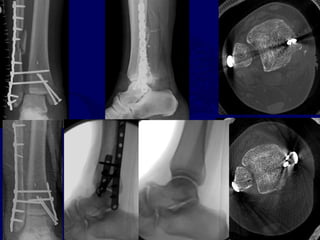

SAD

Consider anteromedial

approach

Marginal impaction

reduction +/- grafting

Medial antiglide plate

Specific articular pathology associated with SA